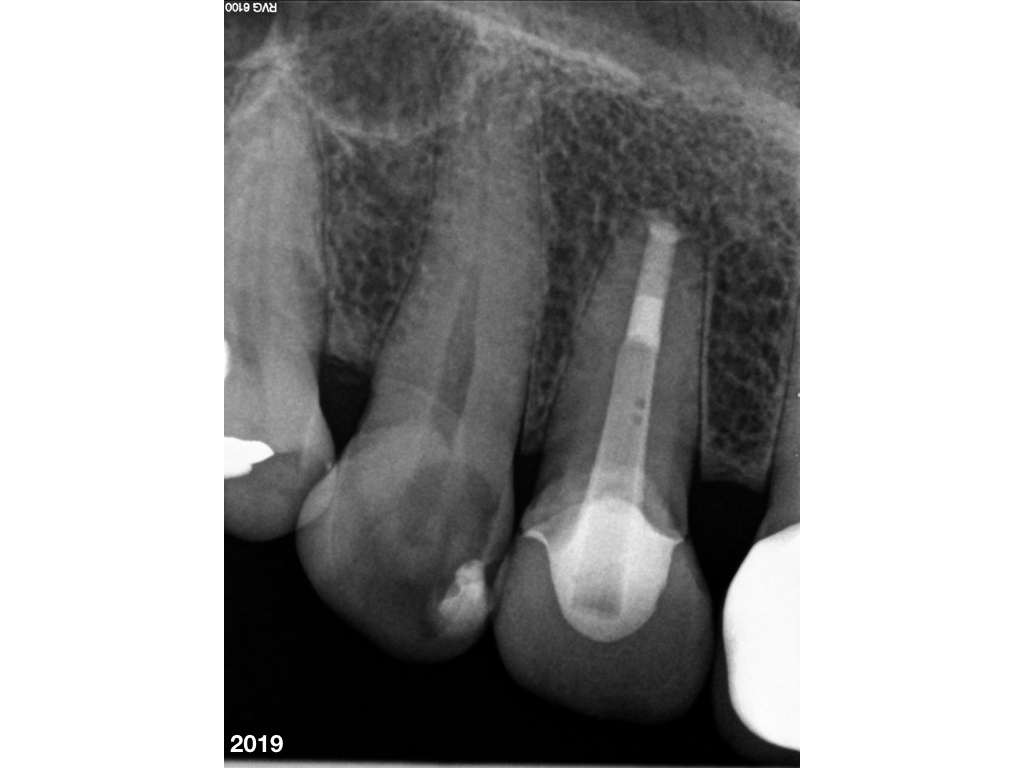

WSR_fast 15Jahre im Recall – WSR (5).004 Veröffentlicht 4. Dezember 2019 am 1024 × 768 in Fast 15 Jahre im Recall – Z.n. WSR (5)